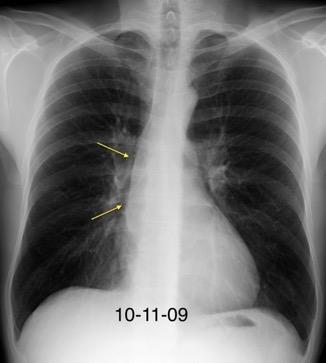

Tromboembolismo pulmonar Diafragma elevado 20%

Nódulos pulmonares múltiples. (flechas verdes). Masas paratraqueales. (flechas amarillas). Dudoso ensanchamiento retrocrural (flechas negras). sigue….

T. mixto de células germinales del testículo

izquierdo Metástasis pulmonares. (flechas verdes). Ganglios paratraqueales. (flechas amarillas). Ganglios retroperitoneales (flechas negras)